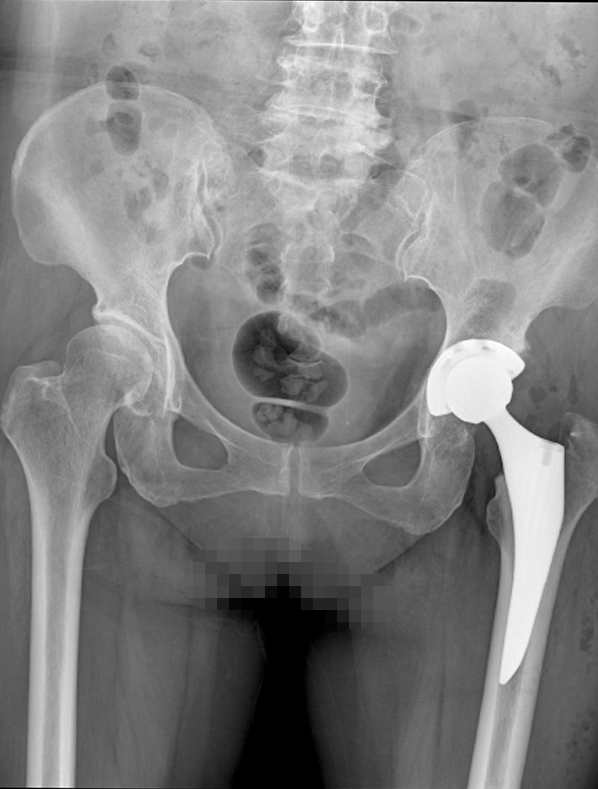

入院后,梅女士继续完善了专科检查、骨盆正位片和磁共振成像(MRI)等检查以明确诊断。我仔细为梅女士查体,左下肢明显短缩约2cm。左侧髋部色泽正常,皮温不高,双侧臀肌轻度萎缩。四肢无肿胀,无静脉曲张,左下肢肌肉轻度萎缩。双侧腹股沟区及髋部无明显压痛,左侧股骨大转子叩击痛(+),左侧足跟轴向叩击痛(-),左侧4字试验(+)。左髋主被动活动度:主被动屈曲95°,主被动过伸0°,主被动内收20°,主被动外展25°,主被动内旋25°、外旋25°;脊柱正常生理弯曲,腰椎棘突无叩击痛,椎旁肌无压痛,双侧直腿抬高试验(-)。骨盆正位片提示主动脉硬化,胸腰椎骨质增生。我考虑为左股骨头无菌性坏死并髋关节退行性骨关节病。继续MRI检查,结果提示右侧髋关节退行性变,双下肢不等长,双侧膝关节退行性变。再结合临床表现,可明确诊断为左侧股骨头无菌性坏死。

我仔细与梅女士沟通治疗方案,诊断明确,保守治疗差。本病的治疗原则是早发现、早诊断、早治疗。治疗开始越早,治疗难度越低、方法也相对更简单;治疗开始得越晚,效果也会越差,建议通过手术进行治疗。患者表示积极配合治疗,入院第4天,继续完善术前准备,梅女士心、肺、肝、肾功能可,常规检查未见明确手术禁忌症。入院第5天,全身麻醉下行左侧全髋关节置换术+髋臼造盖成形术+髋关节松解术+关节滑膜切除术+肌腱粘连松解术,术中见股骨头表面塌陷、变形、增生,髋关节软骨磨损,髋臼边缘骨赘形成。最后以皮肤钉间断缝合皮肤,敷料包扎切口。术毕。全程术野未见明显脓液脓苔或组织水肿。术后安返病房,予5%葡萄糖氯化钠补液、布洛芬镇痛、铝碳酸镁护胃、盐酸甲氧氯普胺注射液止吐、头孢他啶预防感染、补充白蛋白等对症支持治疗。术后第3天,经治疗症状基本得到缓解,且身体恢复良好,精神状态佳,遂通知其家属可办理出院手续。